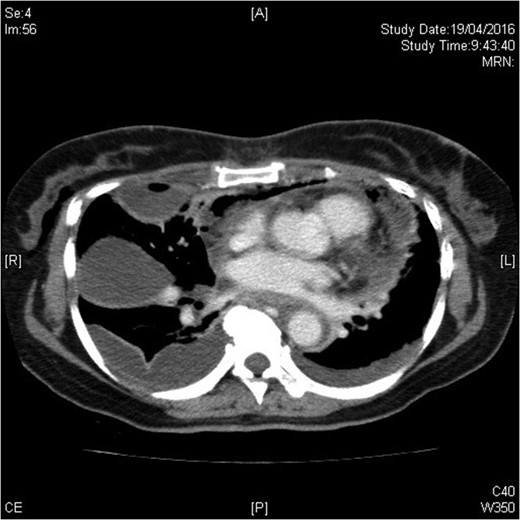

The urgent contrast computed tomography neck and thorax revealed multiple gas locules in bilateral deep cervical spaces, loculated right pleural effusion and right chest wall subcutaneous emphysema. The overall radiological features were suggestive of underlying deep neck space infection by gas-forming organisms complicated with descending mediastinitis and empyema thoracis (see Figs 1–3).

Infection extending down to superior mediastinum and chest wall.